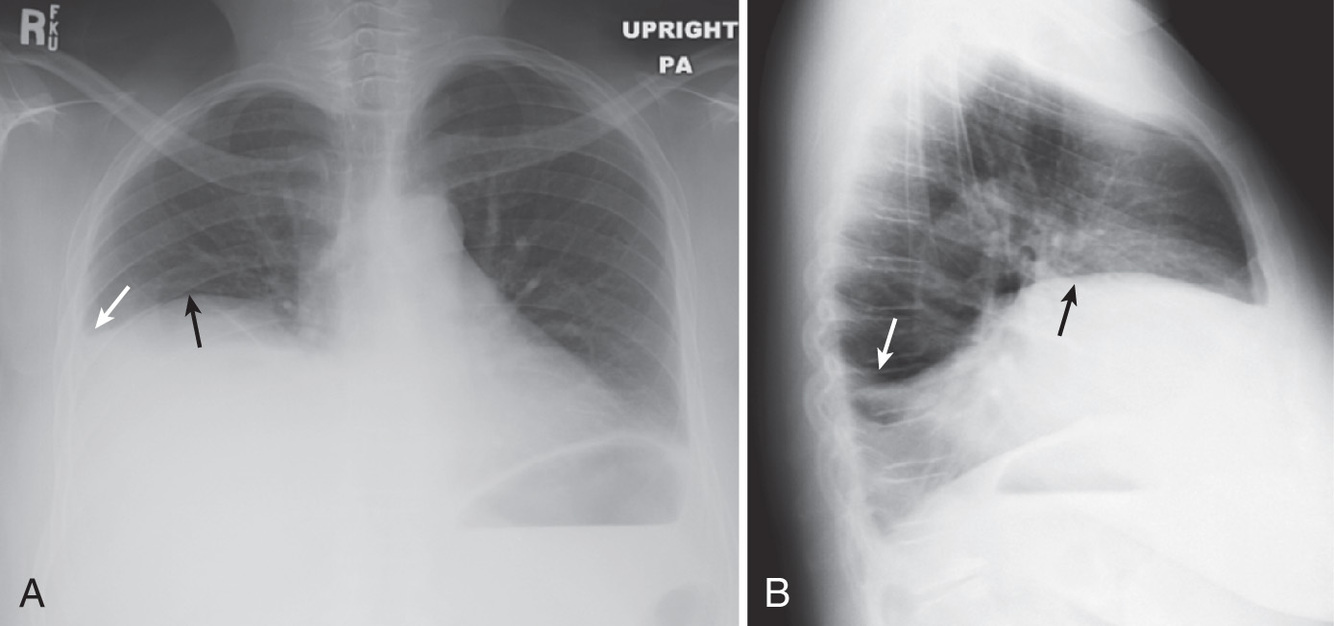

What is going on in this CXR?

These radiographs show atelectasis of the right middle lobe

You can tell that this is atelectasis rather than a consolidation by the downward displacement of the minor fissure

Fissures move towards a collapsed lobe, as do the trachea and heart, and the ipsilateral diaphragm.